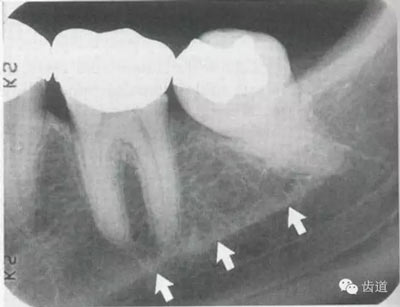

牙槽骨:下牙槽骨密質(zhì)骨厚而松質(zhì)骨少,骨小梁多呈水平方向排列,骨髓腔呈三角形和大小不等的圓形密度低的影像,所以下牙槽骨的骨小梁結(jié)構(gòu)呈網(wǎng)狀結(jié)構(gòu)

位于磨牙牙根尖下方,呈寬約為0.4cm凹面向下邊緣整齊的帶狀密度低的影像,其兩側(cè)有密度高的線條狀影像,為下頜管骨密質(zhì)